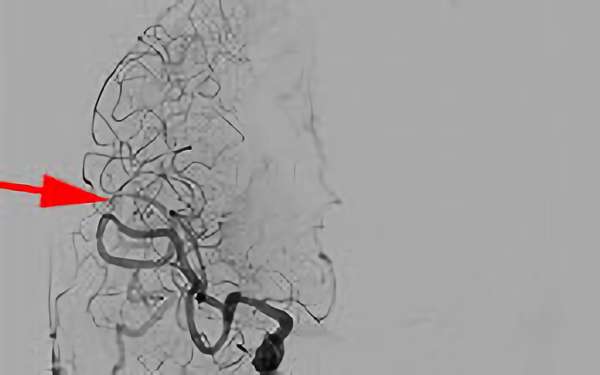

No.1585 手術前

No.1585 手術中

No.1585 手術後